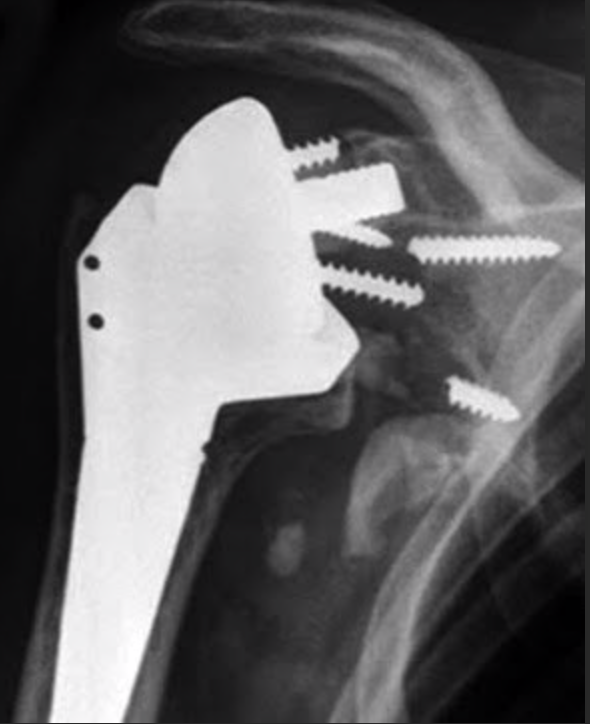

UW Shoulder and Elbow Academy The superior baseplate screw in reverse How Serious Is Shoulder Replacement Total shoulder replacement, also known as total shoulder arthroplasty, is a procedure where portions of the bones in the shoulder joint are removed and replaced with. Arthritis is when the cartilage on the ends of the bones is gone and there is bone rubbing on bone in the joint. There are many options, ranging from. The most common reasons for. How Serious Is Shoulder Replacement.

SHOULDER REPLACEMENT 3 How Serious Is Shoulder Replacement An orthopedic surgeon will replace the natural bone in the ball and socket of your shoulder joint with a. The most common reasons for a shoulder replacement surgery are osteoarthritis, rotator cuff tear arthropathy, avascular necrosis or rheumatoid arthritis. When arthritis or pain in your shoulder becomes severe enough to affect your daily life, you might consider shoulder replacement surgery.. How Serious Is Shoulder Replacement.